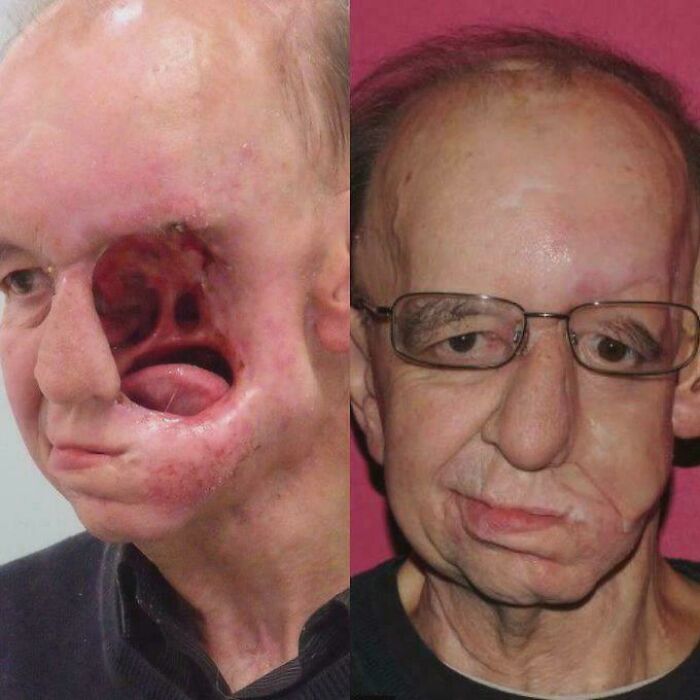

3D Printed Face: When Tech Meets 'Wow!'

Meet Eric Moger, 62, engaged and happy - until doctors found a tennis-ball-sized tumor during a routine surgery. After losing much of the left side of his face to surgery, depression hit hard. But don't worry, this story takes a heroic turn thanks to 3D printing. A special prosthetic mask and mouth implant gave Eric back his smile and his life. Now? Happily married and cancer-free!